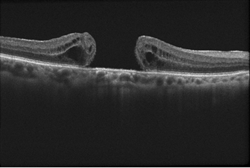

Figure 1.

Optical coherence tomography (OCT) is the current gold standard in the diagnosis, staging, and management of macular holes (Figure 1). This quick, non-invasive imaging technique allows for evaluation of the macula in high resolution using reflected light, and helps your doctor differentiate a hole from other eye conditions with similar symptoms. No laboratory tests are needed in cases of idiopathic macular holes (those without a known cause).

This image was originally published in the ASRS Retina Image Bank. Eric A. Postel, MD, Duke Eye Center. Traumatic Macular Hole. Retina Image Bank 2012; Image 2858. © the American Society of Retina Specialists.